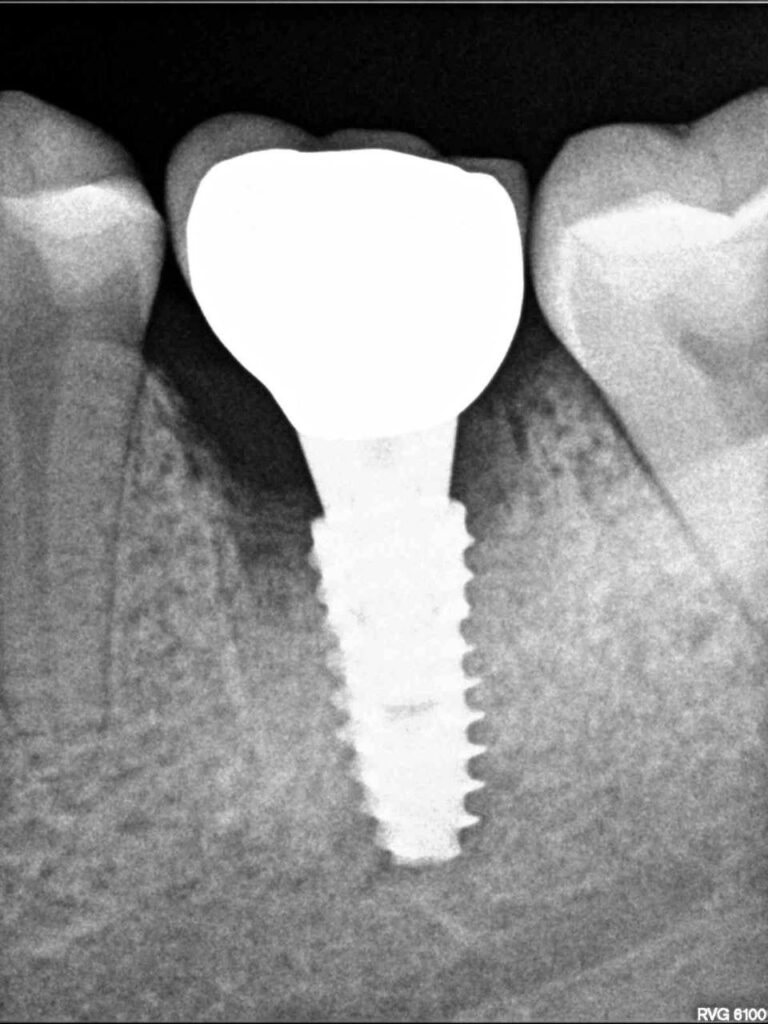

Специализация: терапия(эндодонтия), ортопедия, имплантология.